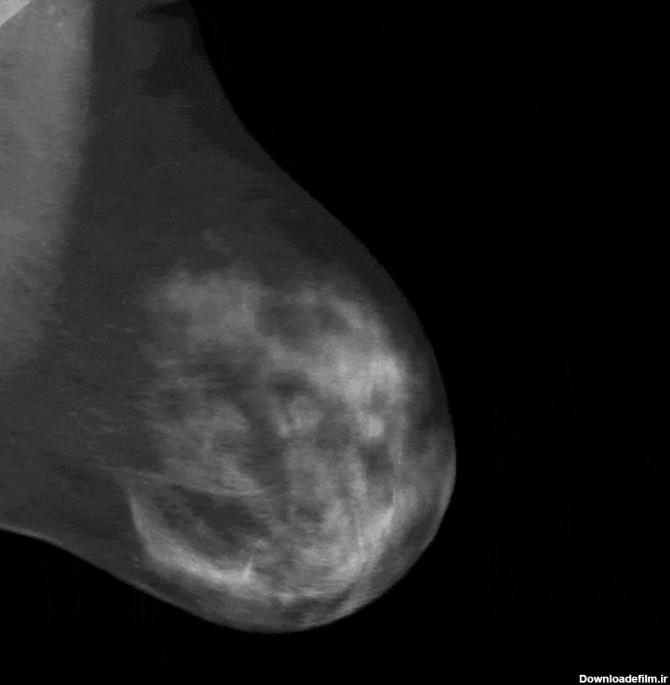

نمونه عکس ماموگرافی

ماموگرافی توانایی پزشک را در تشخیص توده های کوچک افزایش می دهد. وقتی بیماری سرطان در مراحل اولیه باشد احتمال درمان کامل بیماری بسیار بالا است.. استفاده ازماموگرافی تشخیص رشد غیر طبیعی بافت درون مجاری شیری را امکان پذیر می سازد. این تومورهای سرطانی در صورتیکه در مراحل اولیه جراحی و خارج شوند آسیب چندانی برای فرد ایجاد نمیکنند. ماموگرافی تنها روش ثابت شده تشخی ... | انجام کلیه امور مربوط به سونوگرافی، رادیولوژی، ماموگرافی، پانورکس و سنجش تراکم استخوان به صورت دیجیتال واقع در غرب استان تهران (شهرک اکباتان)